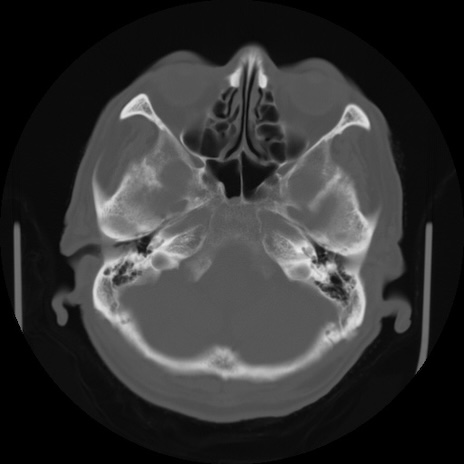

【頭部】症例5 CT(横断像)

症例5の画像所見と診断は?

CT(矢状断像)